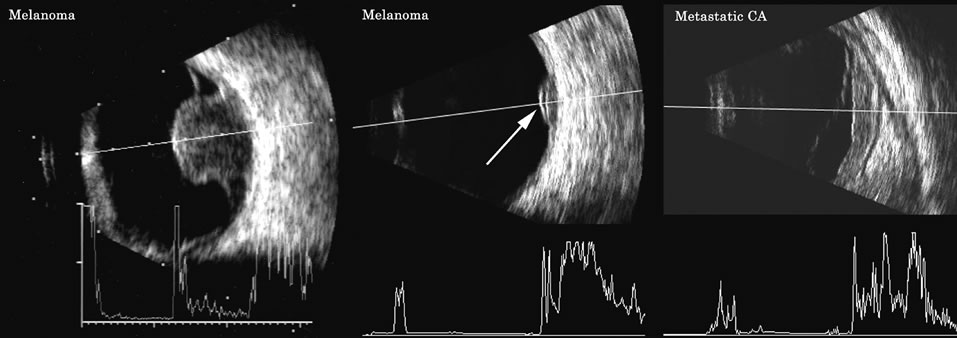

Malignant melanoma varies in its ultrasound presentation from a relatively homogeneous to heterogenous lesion on B-scan. The typical uveal melanoma absorbs sound so that the posterior section is relatively less echoic than the anterior aspect, producing a gradually decreasing amplitude, often to baseline on the A-scan (Fig. 21).

Melanomas also have varying amounts of melanin, a highly acoustically reflective pigment. As noted, melanomas characteristically show high reflectivity anteriorly, with decreasing reflectance as the sound traverses the tissue. This produces the decreasing amplitude posteriorly in the tumor seen on A-scan and gray-scale B-scan. This effect often enhances the anterior scleral boundary. The posterior tumor border is thus measured as the first “rising” echo from the tumor decline, and it is most easily seen and accurately identified on B-scan.27

Metastatic carcinoma is more heterogeneous, producing a more uniform A-scan amplitude of roughly 50% to 80% of the “scleral” echo amplitude (see below) behind the tumor (Fig. 22). Hemangioma is a very highly reflective tumor with high amplitude all the way through the tumor of 80% to 100% of scleral echo amplitude (Fig. 23).

Fig. 22. Some hemangiomas and metastatic carcinomas may simulate a melanoma. They are differentiated on the basis of a very high amplitude internal echo complex for the hemangioma, a moderately low but sustained echo pattern for the metastasis, and an A-scan with decreasing reflectance as the tumor thickness is traversed. In the center scan of a melanoma, note the double anterior layer caused by edema fluid underlying the crest of the melanoma (arrow).